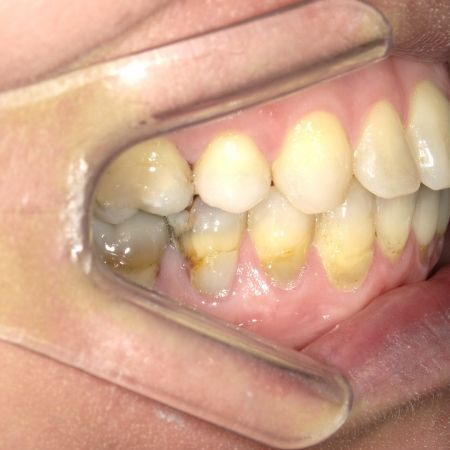

Röntgenbefunde

Links Röntgenbefund vor der Behandlung, rechts Zustand während der Behandlung. Die Lücke im Unterkiefer rechts (linke Seite auf dem Röntgenbild) wurde durch Vorbewegen und Aufrichten des endständigen (wurzelgefüllten) Backenzahnes geschlossen. Prothetische Maßnahmen wurden dadurch überflüssig, außerdem verbesserten sich die Verhältnisse für den Zahnhalteapparat dieses Zahnes deutlich. Der Weisheitszahn im Unterkiefer links wurde vor der chirurgischen Vorverlagerung des Unterkiefers entfernt, um eine ungünstige Trennung der Knochenfragmente zu vermeiden.